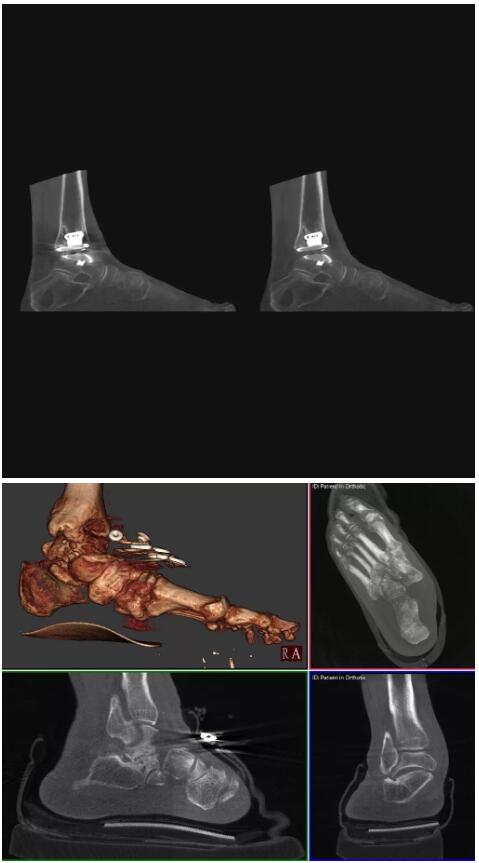

比如上面這款專用于足部和踝部掃查的CT成像系統(tǒng),患者在進行CT掃查時只需要站在上面即可,雙腳站或者單腳站都可以,當然,如果患者不是那么方便站著做完CT掃查,也可坐在上面。

這款CT掃查系統(tǒng)自帶屏蔽裝置,它的體積非常小,僅需要極小的空間即可,并不像常規(guī)CT那樣需要一間單獨的檢查室。此外,這種CT掃查的速度非???,僅需30秒左右可以完成檢查,輻射劑量相對常規(guī)的CT要少許多,尤其適合醫(yī)院的骨科使用。

而患者站著做足部或者踝部做CT檢查還有個好處是,可以檢查患者在負重的情況下,骨關(guān)節(jié)的真實情況,而躺著做CT掃查時未必能看出來。負重CT掃查特別是對于受傷的運動員或者舞蹈員來說意義更大,能夠更準確地評估傷情,幫助他們盡早復原。

以上介紹的CT均來自國外同一家公司,這些CT均配置了可視化軟件,可以進行切片、3D重建以及大型CT附帶的所有典型的操作功能。

以下是這些“特立獨行”的CT所拍出來的圖像: